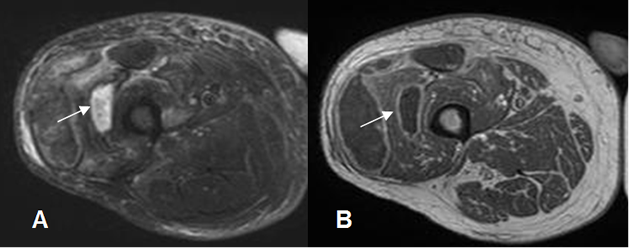

Fig 125. Infección.

A: RM axial en STIR y B: RM axial en T1 con contraste. Igual paciente anterior. Infección postquirúrgica de tejidos blandos, los cuales están edematizados. Hay colección líquida, cuyos bordes realzan con el contraste, por la formación de absceso.